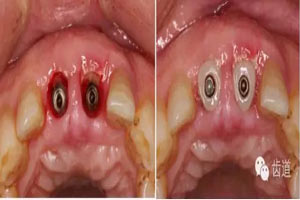

小直徑愈合基臺(tái)就位后唇側(cè)植骨

更換大直徑愈合基臺(tái)

制作個(gè)性化愈合基臺(tái)(參考原牙頸部外形)

換用個(gè)性化愈合基臺(tái)(術(shù)后一周)

半年后復(fù)診(牙齦袖口)